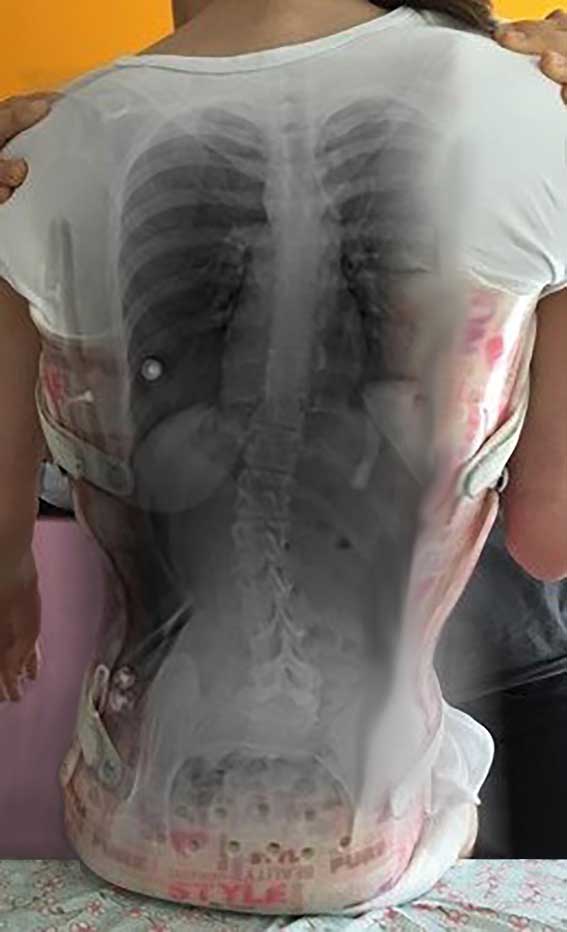

Standardisierte anterior-posteriore (a.-p.) Röntgenbilder wurden retrospektiv ausgewertet. Die Aufnahmen wurden bei allen Patienten in sitzender Position durchgeführt. Bei 3 Patienten wurden Röntgenbilder in stehender Position angefertigt. In liegender Position angefertigte Röntgenbilder waren nicht zulässig, da das maximale Ausmaß der Verkrümmung in dieser Position durch die fehlende Schwerkraft nicht sichtbar ist. Anhand der a.-p. Röntgenbilder wurden der Apex sowie die lumbalen und thorakalen Cobb-Winkel berechnet. Alle Winkel wurden mittels „Centricity Dicom Viewer V3.1“ gemessen. Bei demselben Krankenhaustermin wurden zwei Röntgenbilder angefertigt: eine erste Röntgenaufnahme (T1) mit Doppelschalenkorsett und nach 5 Minuten (T0) ein zweites Röntgenbild ohne Korsett. Dies war allerdings nur bei Patienten mit korrekter Anpassung des Doppelschalenkorsetts möglich. Bei den anderen Patienten betrug die Zeitspanne zwischen T1 und T0 nicht mehr als 3 Monate aufgrund notwendiger Anpassungen des Doppelschalenkorsetts durch den Orthopädietechniker. Der Grad der Korrektur des Cobb-Winkels im Bereich der Lenden- und Brustwirbelsäule wurde in Prozent des Messergebnisses ohne Korsett bei T0 ausgedrückt (Abb. 1 u. 2).

In allen Fällen wurde, wie von Rutz et al. im Jahr 2013 39 beschrieben, ein Doppelschalenkorsett verwendet. Es handelt sich um ein maßgefertigtes Korsett (Abb. 1), das einfach zu handhaben ist. Das Doppelschalenkorsett besteht aus einer vorderen (ventralen) und einer hinteren (posterioren) Schale. Diese beiden Teile sind je ca. 6 mm dick. In der Regel funktioniert das Korsett mittels Druckpelottensystem, wobei eine gute Beckenfassung essentiell ist. Darüber wird zunächst die hintere Schale aus 5 mm starkem PE tiefgezogen. Diese sollte den Rumpf zu ca. 60 % umschließen und wird nach vorne ausgedünnt. Darüber wird eine vordere Schale gezogen, die großzügig gefenstert wird, um Nahrungsaufnahme und Verdauung nicht zu beeinflussen. Der vordere Rahmen dient vornehmlich dazu, den Körper in der hinteren Schale zu fixieren. Damit die Position zwischen vorderer und hinterer Schale sicher reproduziert werden kann, werden an der hinteren Schale Führungsbolzen angebracht und in der vorderen Schale Führungsschlitze vorgesehen. Eltern bzw. Pflegern wurde empfohlen, das Doppelschalenkorsett über einen Zeitraum von 6 bis 8 Stunden pro Tag am betroffenen Patienten in Positionen anzuwenden, in denen die Schwerkraft Einfluss auf die Wirbelsäulenverkrümmungen nehmen kann, also z. B. in sitzender oder stehender Position, aber nicht während des Schlafes oder im Liegen.

- In Seitenlage: Bei diesem Verfahren lag der Patient auf der konvexen Seite der Skoliose. Der Abdruck wurde von zwei erfahrenen Orthopädietechnikern vorgenommen. Die Hüfte war 70° flektiert. Abbildung 2 zeigt diese Position (Kopf auf der rechten Seite). Auch hier wurde der Abdruck eingescannt und am Bildschirm weiterbearbeitet.

Die Abbildungen 3 und 4 zeigen die klinischen und radiologischen Befunde für eine 18-jährige Frau (Fall 17). In Abbildung 3 sind die klinischen Fotos ohne und mit Doppelschalenkorsett zu sehen. Abbildung 4 zeigt die Röntgenbilder dieser Patientin ohne (a) und mit (b) Doppelschalenkorsett.